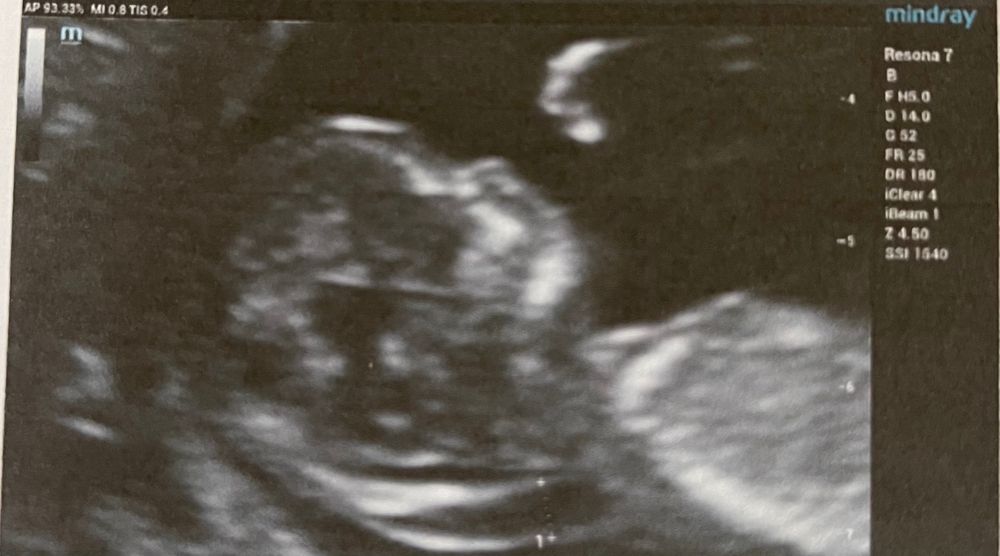

По узи вроде все хорошо , но твп 3,5 мм :( про носовую кость написано так - есть хипопластический ( честно , в интернете ничего толкового не нашла ) . Расчёт риска - трисомия 21- 1:209 . Во вторник буду сдавать биопсию хориона . Не знаю как дожить до этого дня 😫

может кто по узи может сказать , косточка есть или нет ? И что может означать хипопластический 🙏🏼

носик есть

Дай Бог , чтобы у малыша все было хорошо!!! На снимке, мне кажется, у вас хорошенький носик, но я не врач... Всего Вам наилучшего и поменьше нервов.

Успокойтесь,риск 1 к 209 это не так страшно,у меня был риск в предыдущую беременность 1 к 5 и шикарная носовая кость (итог синдром дауна после забора чорсин хориона подтвердили), я вот вижу у вашего малыша носовую косточку,она светится белым на узи, в любом случае удачи вам,я очень надеюсь,что малыш здоров у вас🙏🙏

Буду мамой , не расстраивайтесь раньше времени! ТВП 3.5 не так много, при СД все таки эти цифры ближе к 6, нос может быть просто очень маленьким, может у вас в роду курносый кто, у курносых деток носовая косточка может быть совсем маленькой, здесь были такие случаи, малыши рождались с носиком пуговкой